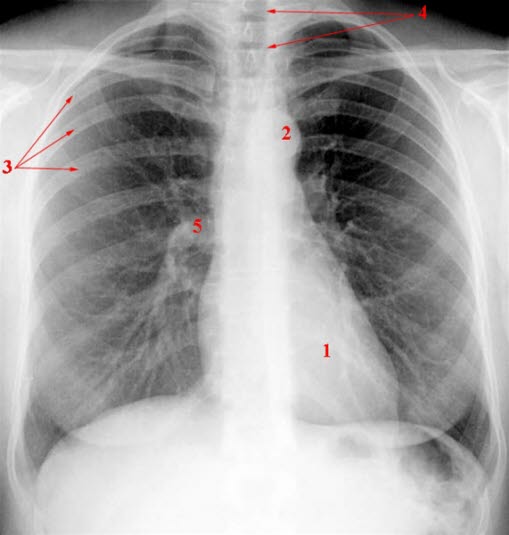

Thorax normalt

1. Hjerteskygge

2. Aortabue

3. Costae (ribben)

4. Trakea (luftrør)

5. Lungehilus